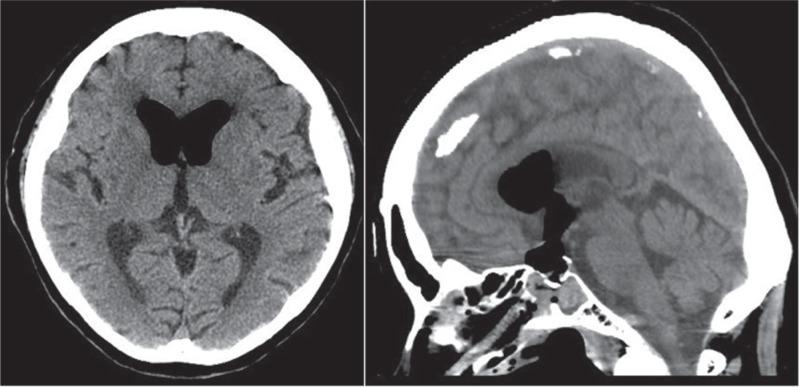

Persisting embryonal infundibular recess (PEIR) is a rare anomaly of the third ventricular floor. Only eight cases have been published. In this report, a case of presumably Rathke's cleft cyst associated with cerebrospinal fluid leakage caused by PEIR is described. An 81-year-old woman underwent endoscopic transsphenoidal surgery for the intra- and supra-sellar cystic lesion. Intraoperatively a hole was confirmed over the sella turcica connecting the sellar cyst and the infundibular recess. Liquorrhea did not occur throughout the procedure. A computed tomography (CT) scan obtained immediately after surgery disclosed accumulation of air in the third and lateral ventricles, in addition to the intra- and supra-sellar region. Air accumulation resolved spontaneously after bed rest for 11 days and she was discharged without neurological deficits. However, she required the second transsphenoidal surgery to repair the sellar floor because of bacterial meningitis caused by liquorrhea on the postoperative day 23. A postoperative 3-tesla magnetic resonance image revealed a deep infundibular recess connecting the sella turcica and the third ventricle, which was considered to be PEIR. To the best our knowledge, this is the first reported case describing the intraoperative findings of PEIR.

持续性胚胎漏斗隐窝(PEIR)是第三脑室底部的一种罕见异常。仅八例病例被报道。在本报告中,描述了一例可能为拉克氏裂囊肿并伴有由PEIR引起的脑脊液漏的病例。一名81岁女性因鞍内和鞍上囊性病变接受了内镜经蝶窦手术。术中证实蝶鞍上方有一个孔连接蝶鞍囊肿和漏斗隐窝。整个手术过程中未发生脑脊液漏。术后立即进行的计算机断层扫描(CT)显示,除鞍内和鞍上区域外,第三脑室和侧脑室内有气体积聚。卧床休息11天后,气体积聚自行消散,她出院时无神经功能缺损。然而,术后第23天,由于脑脊液漏导致细菌性脑膜炎,她需要进行第二次经蝶窦手术修复蝶鞍底部。术后3特斯拉磁共振成像显示一个连接蝶鞍和第三脑室的深漏斗隐窝通道,被认为是PEIR。据我们所知,这是首例描述PEIR术中发现的病例报告。